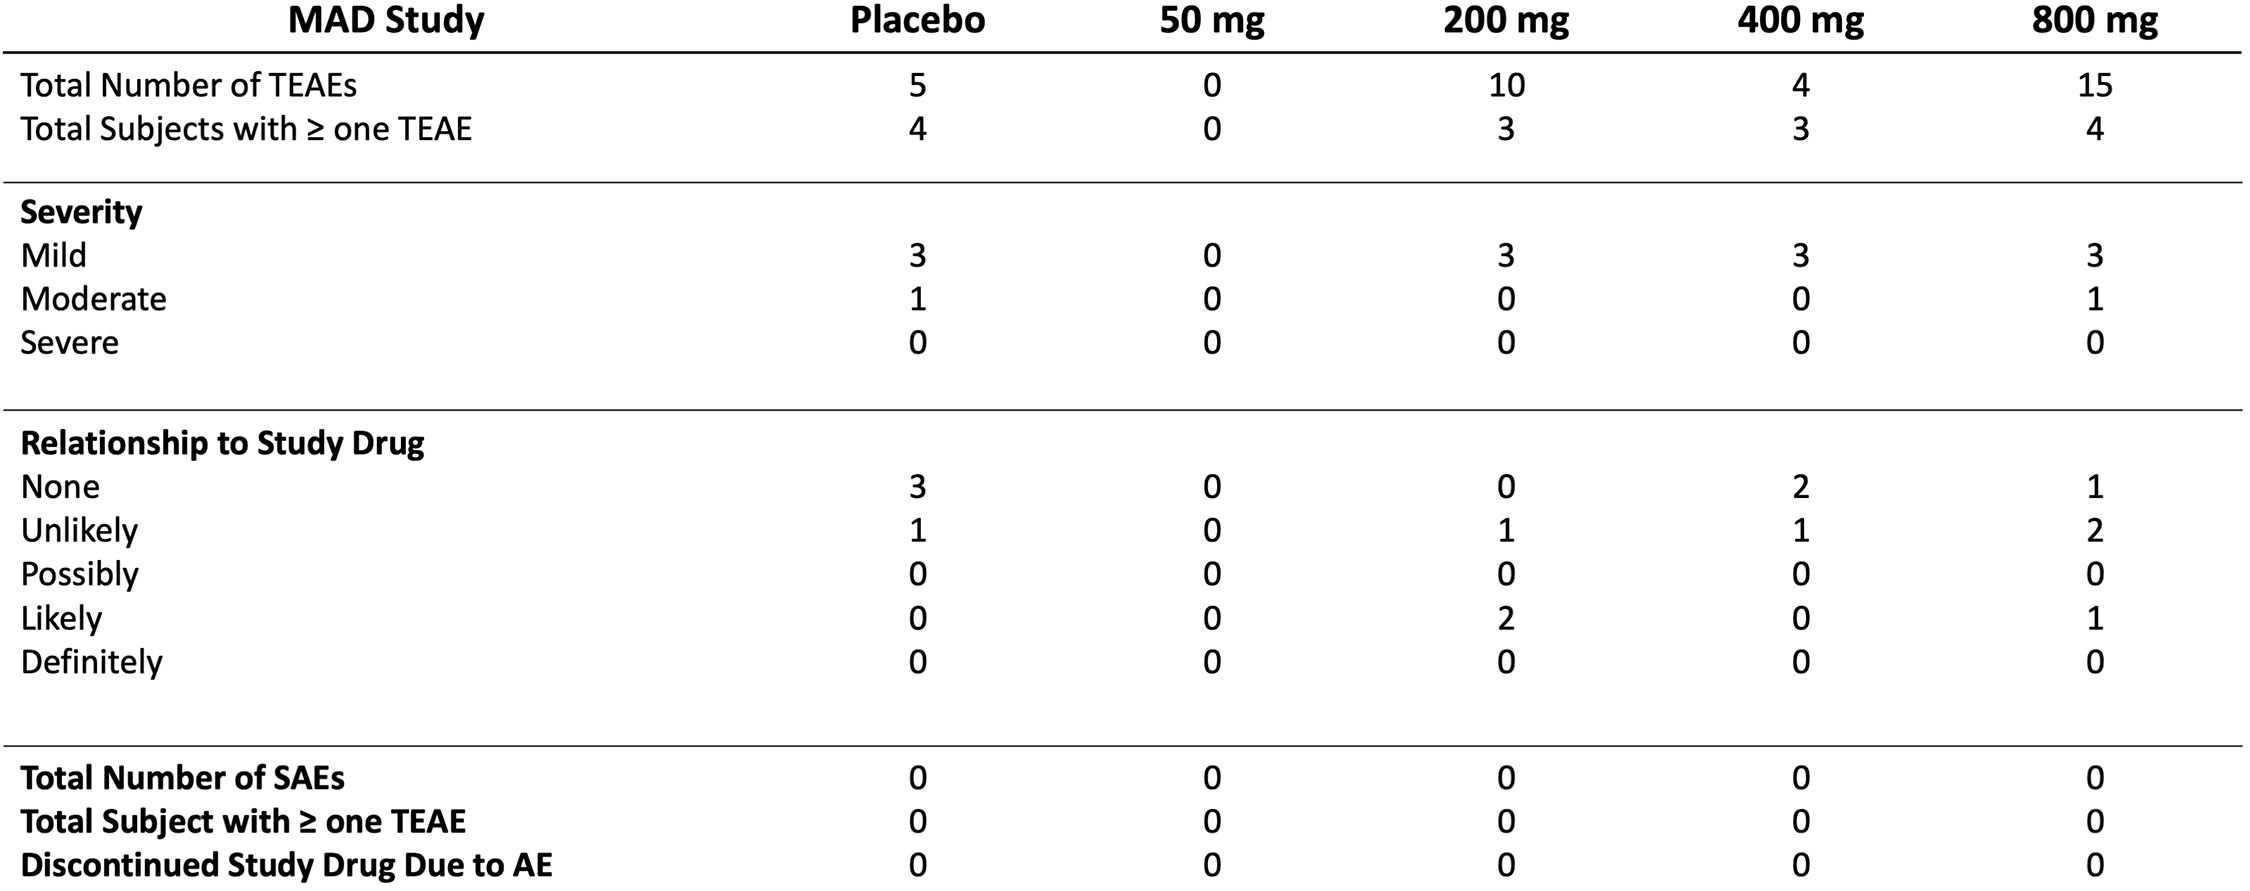

•Completed a Phase 1 study for REC-3964 in healthy volunteers for the potential treatment of Clostridioides difficile (C. difficile) infection with a favorable safety and tolerability profile